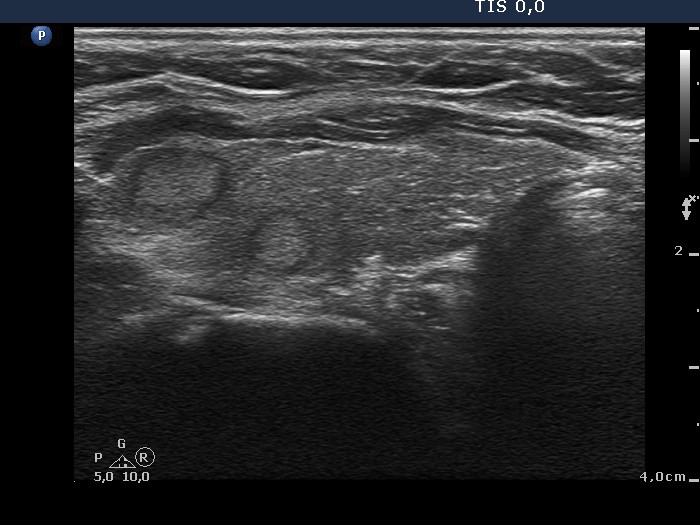

100 consecutive cases of papillary cancer - case 018 (ultrasonographic picture 3)

Right lobe, another longitudinal scan. The two discrete lesions represent those parts of the lobe which are less affected by the underlying thyroiditis.